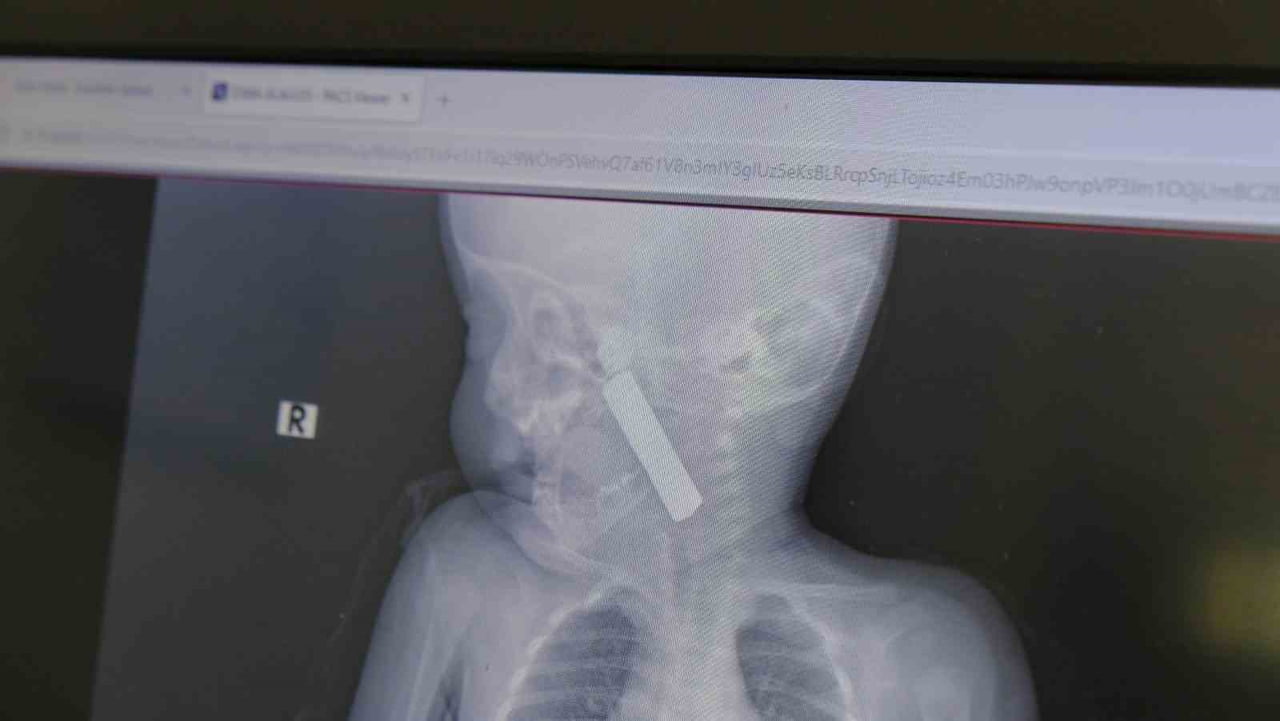

Karaman Eğitim ve Araştırma Hastanesi acil servisine kusma şikayetiyle getirilen 6 aylık E.A. isimli kız bebeğin yapılan muayene ve tetkiklerinde boğazına kumanda pili kaçtığı tespit edildi. Solunum güçlüğü yaşayan bebek, çocuk cerrahisi ekibi tarafından acilen ameliyata alındı.

Yapılan tetkiklerde pilin ağız tabanına oturduğu ve yemek borusunun birinci darlığına kadar uzandığı görüldü. İlk muayenede bebekte belirgin siyanoz ve solunum sıkıntısı vardı; oksijen satürasyonunun yaklaşık 90 civarında olduğu bildirildi. Durum acil olduğundan, ekip vakit kaybetmeden ameliyathaneye yöneldi.